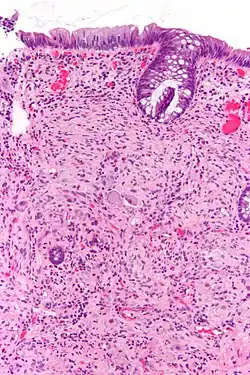

Pathologie

Pathologiquement, les ganglioneuromes sont composés de cellules ganglionnaires, de cellules de Schwann et de tissu fibreux[4]. Les ganglioneuromes sont des tumeurs solides et fermes, généralement de couleur blanche à l'œil nu.